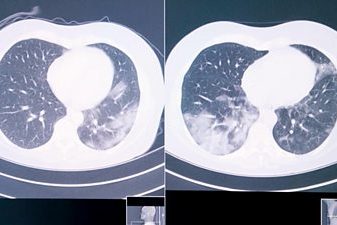

- 6 Как ИИ помогает пациентам с раком легких в эпоху Covid-19